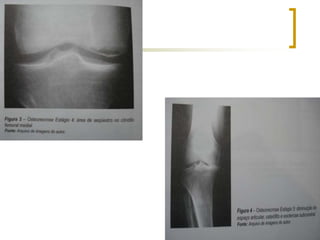

Classificação - Koshino

 Tipo 4: área com placa calcificada,

seqüestro ou fragmento circundado por halo

esclerótico; cintilografia positiva;

 Tipo 5: radiografias com redução do espaço

articular, presença de osteófitos e áreas de

esclerose subcondral - osteoartrose;

cintilografia positiva.

 Tipo 1: radiografias normais e cintilografia positiva, se

nenhuma alteração for observada em 6 meses, permanecerá

neste estágio;

 Tipo 2: radiografias com aplanamento do planalto tibial e do

côndilo femoral e cintilografia positiva;

 Tipo 3: radiografias com áreas de radioluscência, halo

esclerótico no foco de ON e áreas de esclerose distal a este –

Sinal do crescente; cintilografia positiva.